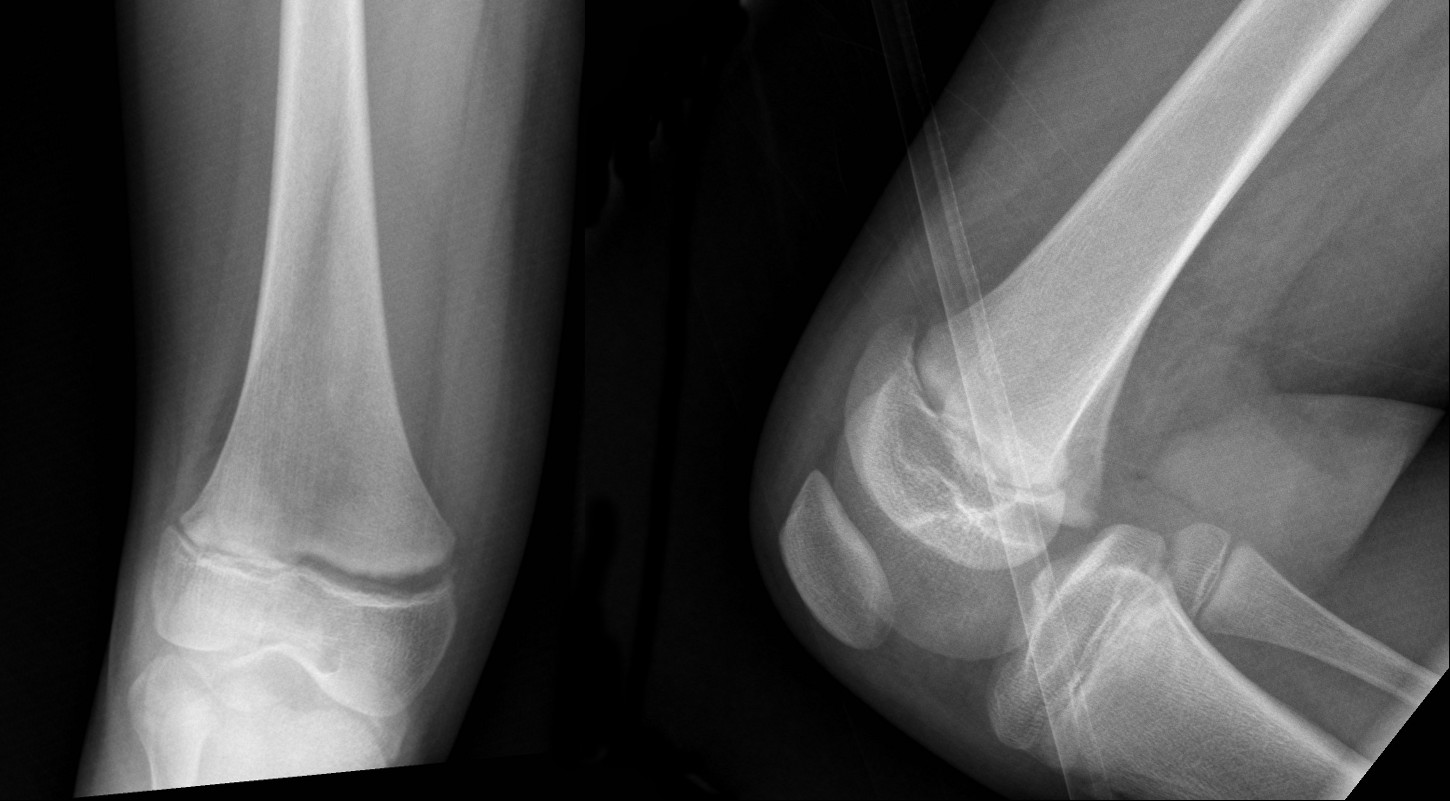

Distal femoral physeal fracture – widened physis with mild anterior displacement. – Salter-Harris I fracture (above).